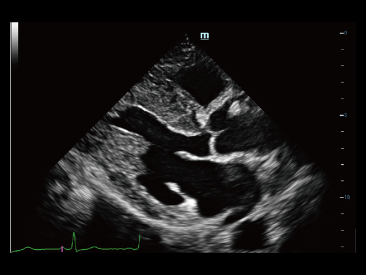

Od czasu kiedy zosta?a za?o?ona, Firma Mindray nieustannie poszukuje nowych sposob├│w na polepszenie precyzji w diagnostyce. Dzi?ki zastosowaniu najbardziej rewolucyjnej technologii ZONE Sonography? Technology, platforma ZST+ zastosowana w aparacie Resona 7 przenosi jako?? obrazu ultrasonograficznego na wy?szy poziom dzi?ki strefowemu uzyskiwaniu obrazu - zone acquisition i obr├│bkce danych kana?owych.

Oprócz uzyskiwania jako?ci obrazu typowego dla aparatów klasy premium, Resona 7 rozszerza mo?liwo?ci klinicznych badań USG dzi?ki rewolucyjnej funkcji V Flow, s?u??cej do oceny hemodynamiki naczyń, a tak?e najlepszej na rynku funkcji inteligentnego, automatycznego uzyskiwania p?aszczyzny na podstawie zestawów danych obj?to?ciowych 3D, umo?liwiaj?cej diagnozowanie stanu Centralnego Uk?adu Nerwowego u p?odu. Aparat Resona 7 ??czy w sobie najbardziej intuicyjn?, wielodotykow? obs?ug? za pomoc? gestów oraz wszystkie kluczowe funkcje kliniczne, co sprawia i? jest prawdziwym liderem we wprowadzaniu innowacji w ultrasonografii.